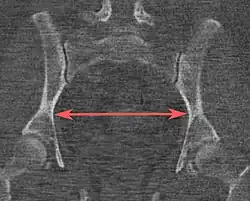

| Pelvic inlet | Transverse diameter of the pelvic inlet |

![]() Coronal plane |

The iliopectineal lines, at widest transverse distance. | 13 to 14.5 cm.[4] |